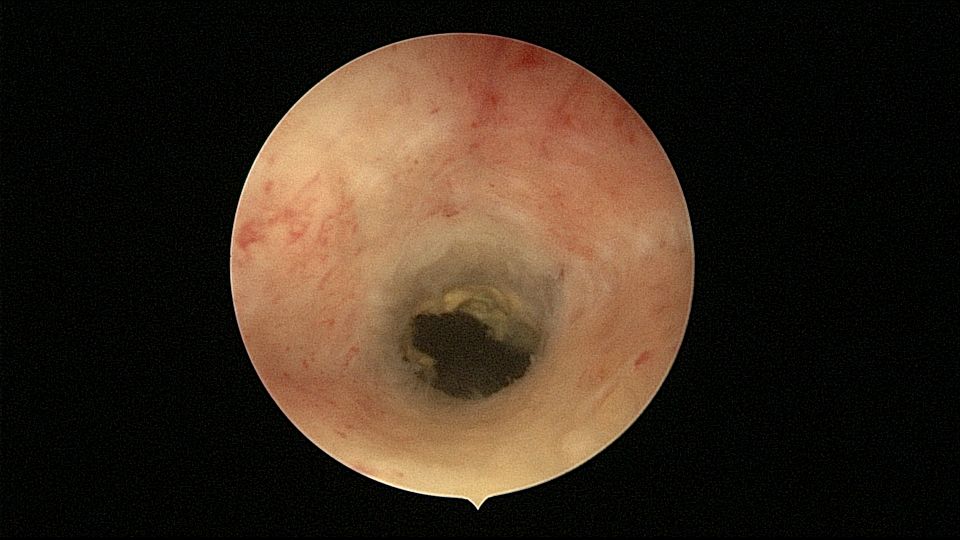

54岁,G2P1,顺产1次,安环16年,绝经10年,无不适症状,B超提示节育器嵌顿,宫腔积液2.3cm*1.9cm,血常规正常,白带常规乳酸杆菌少,其余指标正常。宫腔镜见宫颈管中上段封闭粘连,镜鞘分离粘连,见V型环一臂铜环全部嵌入右侧宫壁肌层内,取出节育器,宫腔内见灰白色脓液漂浮,膨宫液冲洗脓液,宫腔镜下无脓苔后结束手术,术后抗炎治疗。病检:宫腔少许宫内膜,呈慢性炎改变。